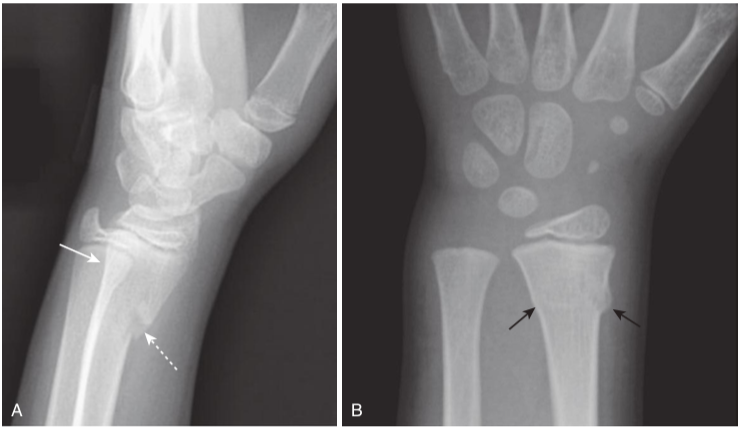

Greenstick and buckle (torus) fractures.

Incomplete fractures are those that involve only a portion of the cortex. They tend to occur in bones that are “softer” than normal, such as those in children (above) or in adults with bone-softening diseases such as Paget disease. A,There is a greenstick fracture, which involves only one part of (dotted white arrow)rather than the entire cortex (solid white arrow). B,This is a buckle fracture, in which there is buckling of the cortex (black arrows).